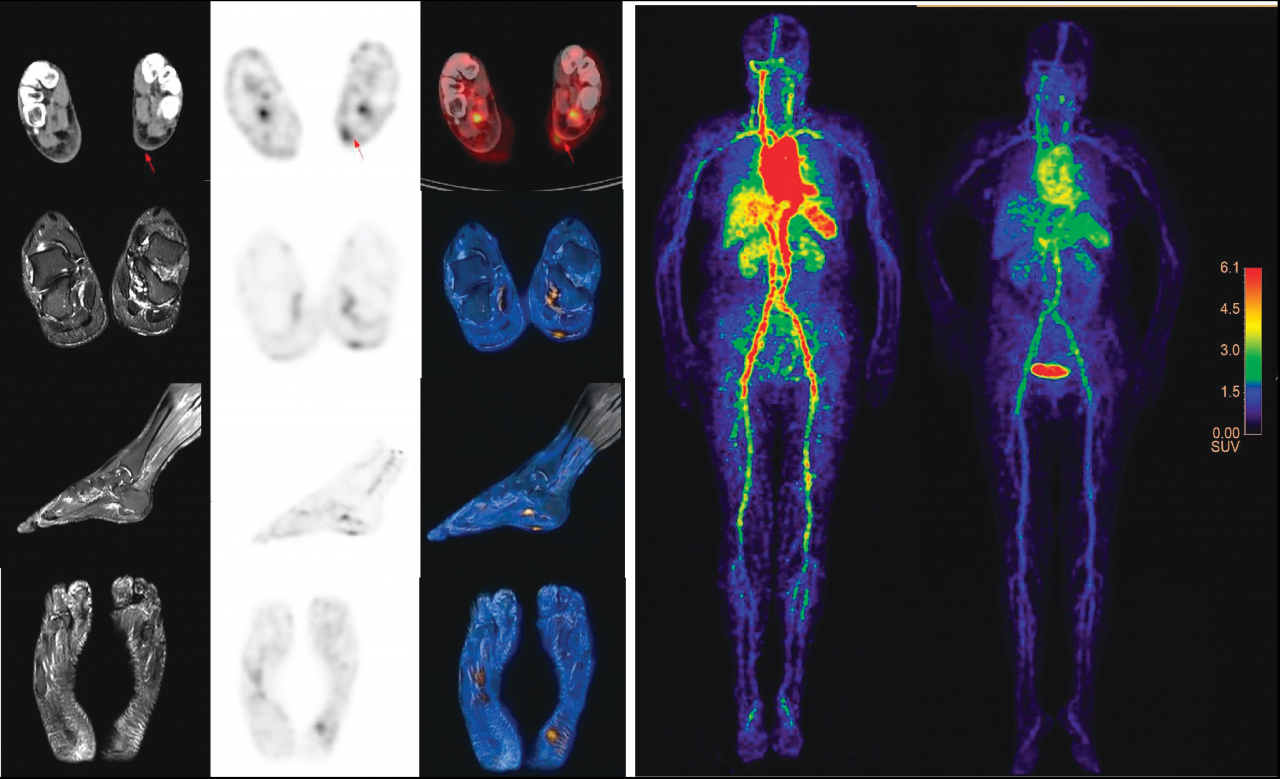

4. 針對腫瘤免疫治療(抗PD-1治療)優(yōu)勢患者篩選及療效評價挑戰(zhàn),研制出新型固體靶核素124I,優(yōu)化出室溫條件60秒快速、原位標(biāo)記單抗技術(shù),實現(xiàn)基于我國NMPA批準(zhǔn)的首個抗PD1治療藥物(JS001, 特瑞普利單抗)的直接放射性標(biāo)記的臨床研究。相關(guān)成果以“Positron Emission Tomography Imaging of Programmed Death 1Expression in Cancer Patients Using 124I-Labeled Toripalimab:A Pilot Clinical Translation Study”為題,于2021年5月發(fā)表在Clinical Nuclear Medicine雜志上。

圖4: I-124標(biāo)記PD1單抗的PET 臨床轉(zhuǎn)化